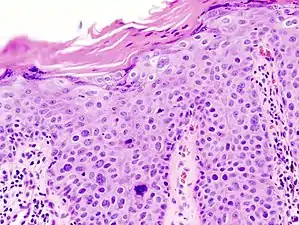

In invasive cSCC, tumor cells infiltrate through the basement membrane. The infiltrate can be somewhat difficult to detect in the early stages of invasion: however, additional indicators such as full thickness epidermal atypia and the involvement of hair follicles can be used to facilitate the diagnosis. Later stages of invasion are characterized by the formation of nests of atypical tumor cells in the dermis, often with a corresponding inflammatory infiltrate.[12]

Superficially invasive cutaneous squamous-cell carcinoma. These lesions often do not show the marked pleomorphism and atypical nuclei of cSCC in situ, but manifest early keratinocyte invasion of the dermis.[12]

High magnification demonstrates the pleomorphism of the invading keratinocytes[12]